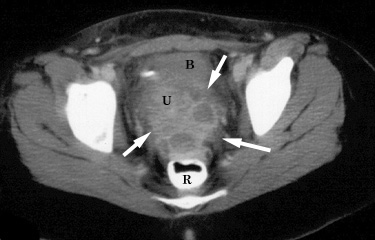

КТ диагностика тубоовариального абсцесса: Подходы и изображения

Раздел: Объективный взгляд